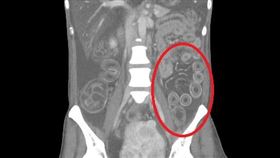

電腦斷層驚胃「20多顆白點」醫問1句秒笑

急診科醫師蔡瀚嶙,時常在自己的社群平台上分享自己遇到...